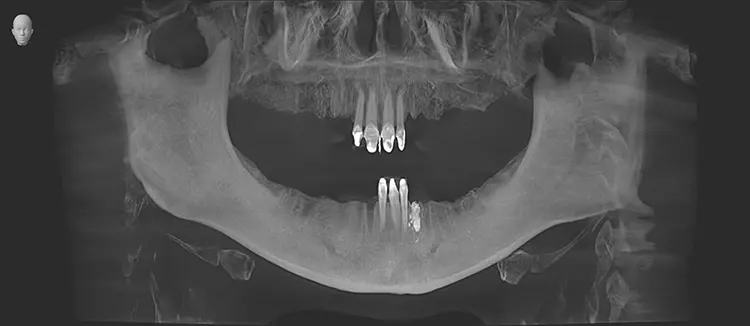

Abb. 18: OPG unmittelbar postoperativ nach Komplettsanierung innerhalb einer

Sitzung in ITN bei stark reduziertem Restgebiss. SDS

Abb. 18: OPG unmittelbar postoperativ nach Komplettsanierung innerhalb einer Sitzung in ITN bei stark reduziertem Restgebiss.

Im weiteren Behandlungsverlauf wurde die Patientin bei einem anderen Vorbehandler bereits festsitzend mit Titanimplantaten versorgt, welche jedoch aufgrund starker lokaler (Schmerzen, Entzündungen) sowie systemischer Reaktionen (u. a. Haarausfall, Hautausschläge) wieder entfernt wurden. Zum Zeitpunkt der Erstvorstellung der folgenden Behandlungsdokumentation war der Restzahnbestand nur noch auf die vier OK-Frontzähne und drei UK-Frontzähne mit voranschreitender Kieferatrophie beschränkt (Abb. 2 und 3).

Die hier vorgestellte 37-jährige Patientin litt bereits seit langer Zeit unter chronisch lokalen sowie undefinierbaren systemischen Schmerzen, was gemäß Angaben diverser Vorbehandler der Patientin funktionell durch ihren Fehlbiss bedingt sei. Regelmäßige Einschleifmaßnahmen hatten bis dahin keine Besserung der Symptomatik zur Folge. Im Jahr 2019 war der generelle Leidensdruck, der laut damaliger Einschätzung von der Mundhöhle ausging, so groß, dass alio loco ein Großteil der natürlichen und wurzelkanalbehandelten Zähne schrittweise extrahiert wurde (Abb. 1).